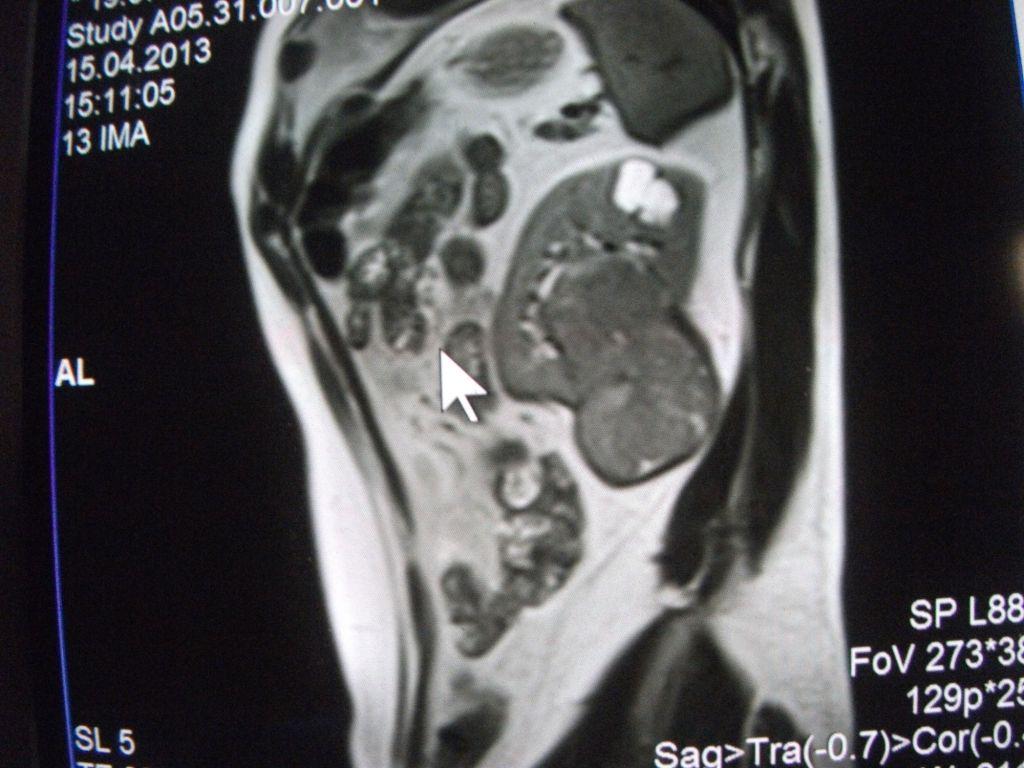

такое заключение: Левая почка: расположена обычно, увеличена, общими размерами около 13х5,5см. В области средней и нижней трети почки определяется объёмное образование неправильной формы, деформирующее наружный контур почки, распространяющиеся с чашечно-лоханочную систему. Опухоль имеет четкие неровные бугристые контуры с наличием псевдокапсулы, неоднородной структуры с признаками распада, максимальными размерами около 78,7х47х48мм